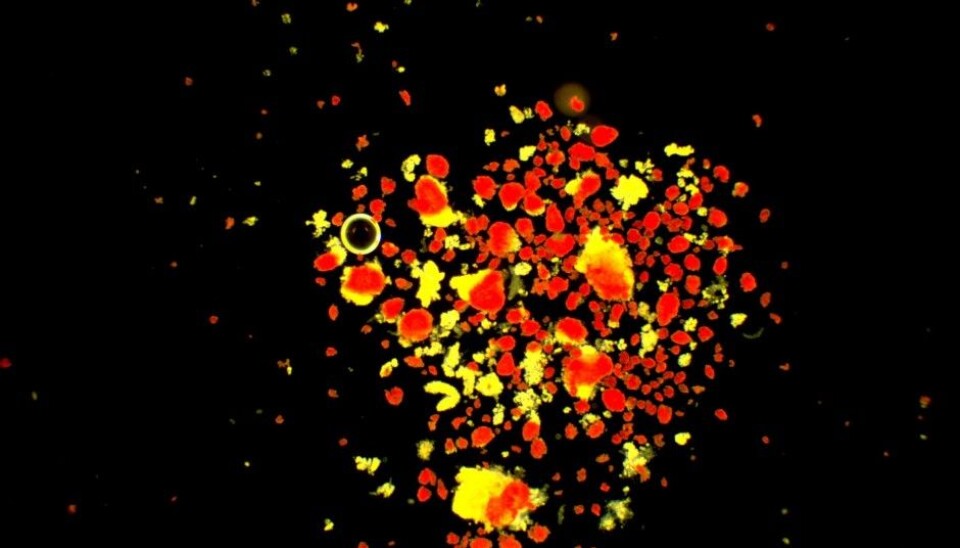

A technique called RNA sequencing was performed on cells from six living and two deceased donors. Sequencing is a way of mapping genes. The results were compared with cells from three healthy donors.

“RNA for all the genes involved in insulin production was found in the tissue samples. We interpret this as meaning that the cellular machinery for producing insulin is still intact. This was confirmed when we saw that the beta cells produced insulin”, says Krogvold.